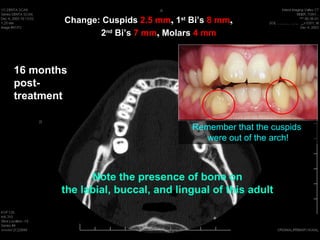

Change: Cuspids 2.5mm, 1st Biโ€™s 8 mm, 2nd Biโ€™s 7 mm, Molars 4 mm 16 months post- treatment 1st Molars โ€“ 4 mm Transverse

Change: Cuspids 2.5mm, 1st Biโ€™s 8 mm, 2nd Biโ€™s 7 mm, Molars 4 mm 16 months post- Roots are upright treatment in bone on both buccal and lingual side after significant transverse movement 2nd Bicuspids โ€“ 7 mm transverse Q: Does this image change your thinking on what is possible?

Change: Cuspids 2.5mm, 1st Biโ€™s 8 mm, 2nd Biโ€™s 7 mm, Molars 4 mm 16 months post- treatment 1st Bicuspids โ€“ 8 mm transverse Q: Does this image change your thinking on what is possible?

Change: Cuspids 2.5mm, 1st Biโ€™s 8 mm, 2nd Biโ€™s 7 mm, Molars 4 mm 16 months post- treatment Observe the presence of bone on the labial, buccal, and lingual of this adult

Change: Cuspids 2.5mm, 1st Biโ€™s 8 mm, 2nd Biโ€™s 7 mm, Molars 4 mm 16 months post- treatment Remember that the cuspids were out of the arch! Note the presence of bone on the labial, buccal, and lingual of this adult

Remember that thecuspids were out of the arch! Evaluate tissue 6 months retention